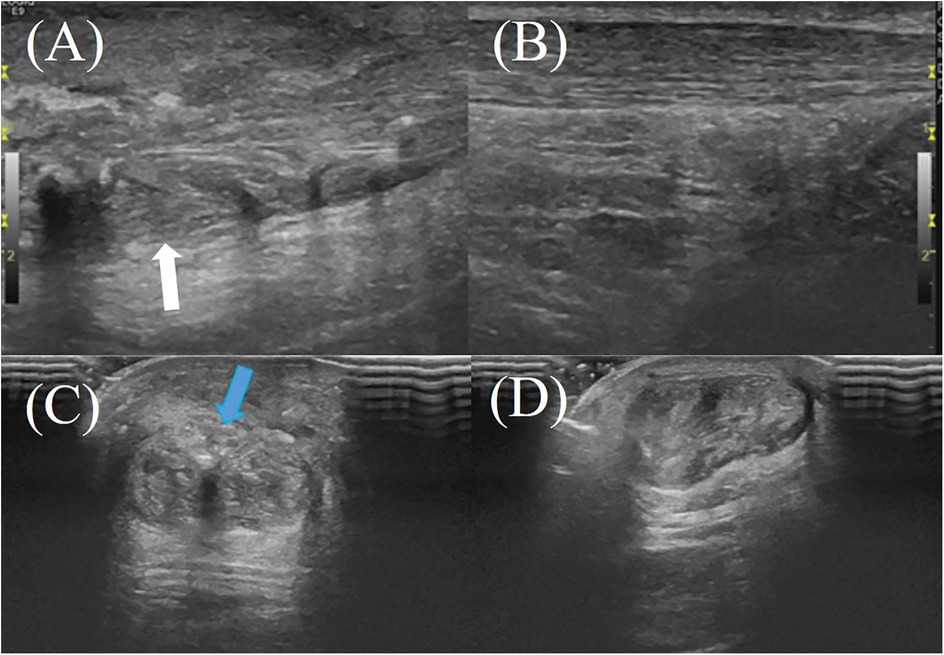

The hAM, composed of multiple collagen types (I, III, V, VI), amniotic epithelial cells, and MSCs, secretes a wide range of bioactive cytokines and growth factors (e.g., TGF-β1, PDGF, IGF, IL-1, IL-10), which contribute to its anti-inflammatory, anti-fibrotic, and regenerative properties (6, 8, 20). In animal models, amniotic membrane application to Achilles tendon injuries has been shown to reduce inflammatory cell infiltration, improve type I and III collagen organization, and significantly enhance biomechanical properties such as tensile strength, stiffness, and cross-sectional area (25, 26) (Figures 2, 3). In contrast, the hAM allograft used in the present study was an acellular, non-vital material, which differs in biological composition from the materials evaluated in previous studies and may therefore not be directly comparable (25, 26). Further studies are needed to determine whether these differences influence clinical outcomes.

Figure 3. A 61-year-old male patient with right Achilles tendon rupture located 3.0 cm proximal to the calcaneal insertion underwent surgical repair without amniotic membrane augmentation. At the 2-month postoperative follow-up, ultrasound evaluation revealed: (A) the repaired tendon on the right side (white arrow) demonstrating heterogeneous echotexture on the longitudinal plane; (B) the healthy contralateral (left) Achilles tendon on the longitudinal plane; (C,D) the repaired right Achilles tendon on the transverse plane, showing irregular hyperechoic signals near the superficial tendon surface, indicating tendon fibrosis or degenerative changes (blue arrow).